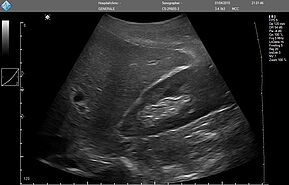

Исследование FAST (Сфокусированная сонографическая оценка при травме) позволяет выявить наличие жидкости в предполагаемых клинических условиях, визуализируя 10 структур или пространств в четырех областях:

- Перикардиальной

- Околопеченочной

- Околоселезеночной

- Тазовой

E-FAST (расширенный-FAST) дополнительно обследует переднюю и боковую плевральную полость (торакальная проекция) для оценки наличия пневмоторакса или плеврального выпота, предположительно гемоторакса у пациентов с травмой.